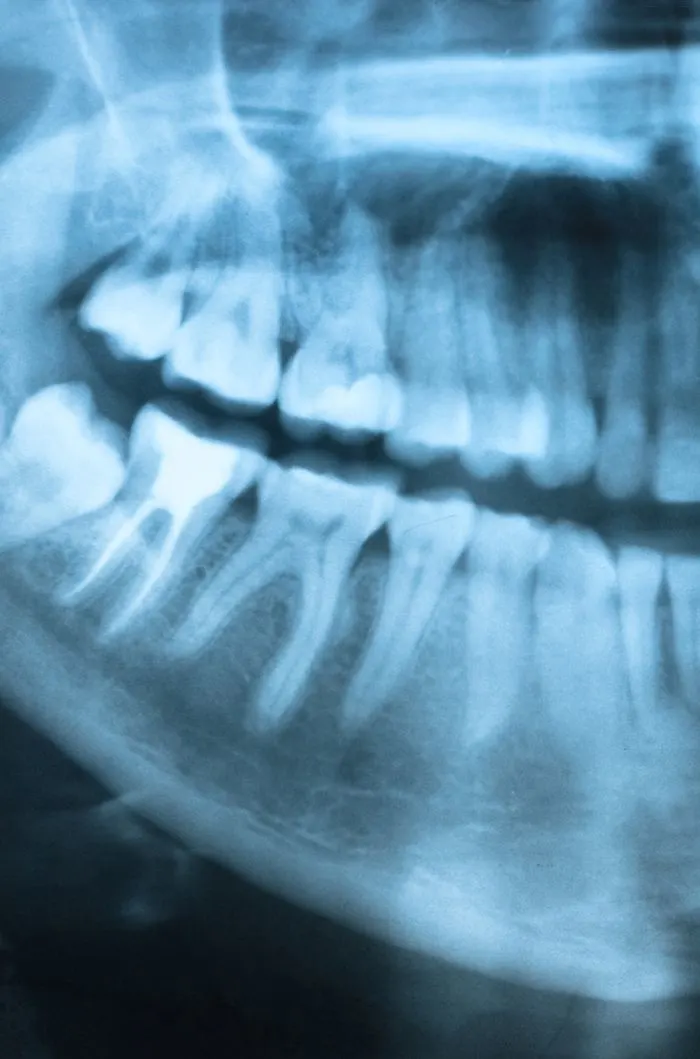

Necessary X-Rays